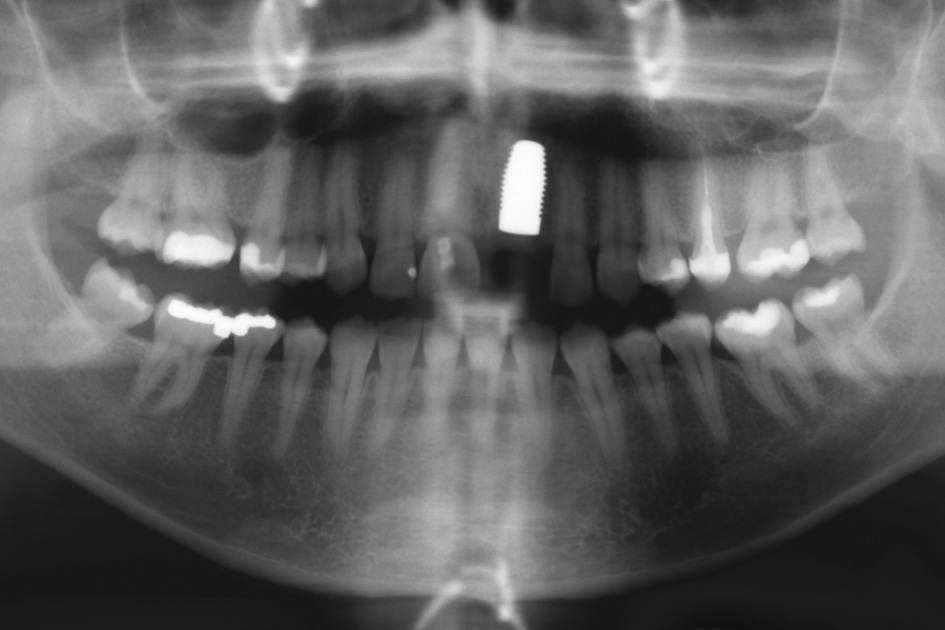

Gleichzeitig mit der prothetischen Versorgung des Implantats wurde auch für Zahn 11 ein Veneer geplant. Zum Einsatz kam ein Zeramex T Implantat Durchmesser 5,5 mm, Länge 12 mm. Für die Kronenversorgung wurde ein mit e. Max überpresstes CAD-Abutment gewählt. Während der Einheilphase des Implantats kam eine Sunflex-Prothese zum Einsatz.